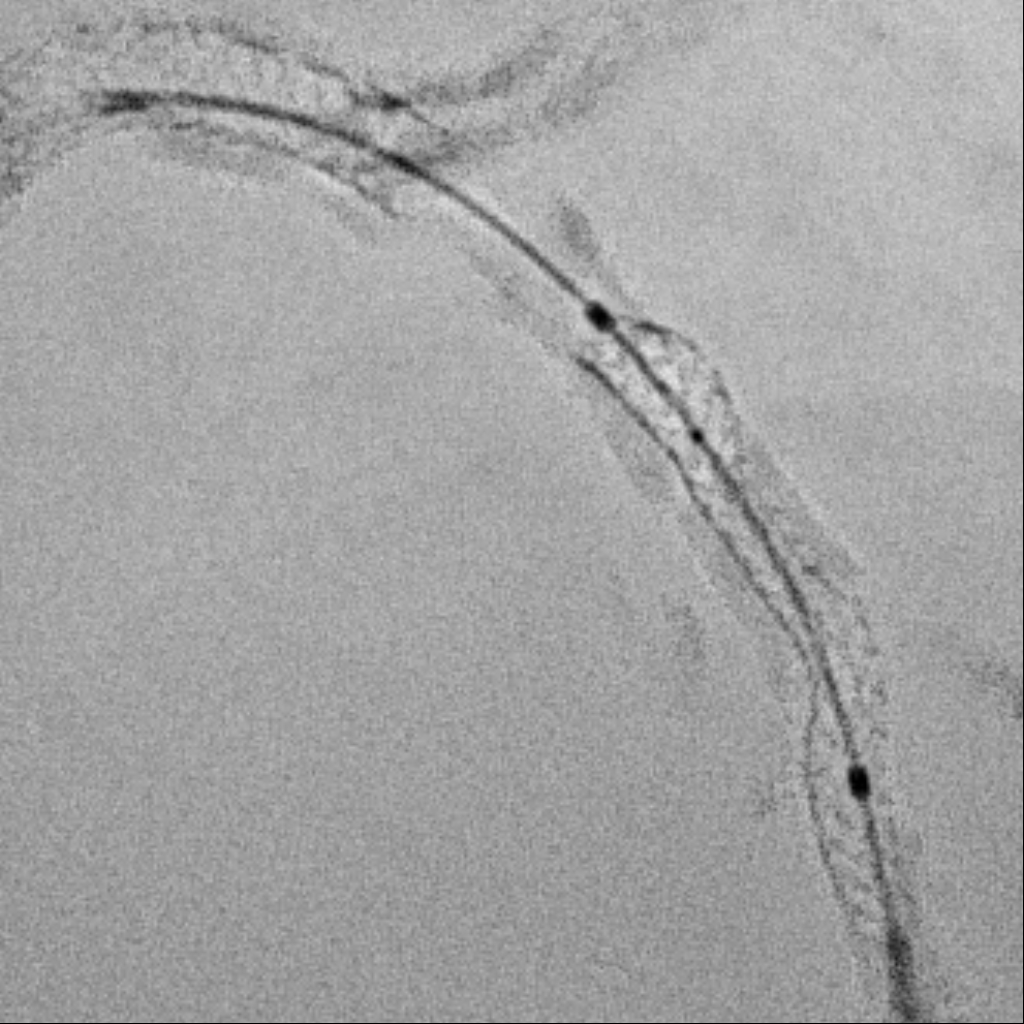

Under IABP (left femoral), PCI via right brachial with 6 Fr EBU 3.5. Runthrough to LAD, Sion Blue to LCX. Predilation of LM/pLAD with 2.0¡¿20 mm balloon; IVUS pullbacks. Further dilatation with 2.5¡¿20 mm NC for mLAD underexpansion, pLAD, and LM. oLCX de novo and pLCX edge ISR predilated with 2.5¡¿20 mm NC; LCX ISR treated with DCB 2.5¡¿20 mm. Szabo technique attempted for LM–LAD with a 3.0¡¿24 mm DES; the undeployed stent dislodged during repositioning and was deployed at the dislodgement site. IVUS showed 2–3 struts protruding into the aorta from the LM ostium and incomplete pLAD coverage. Post-dilation with 3.5¡¿20 and 2.5¡¿20 mm NC; DCB 3.0¡¿20 mm for pLAD uncovered plaque and mLAD proximal edge ISR. Final CAG: TIMI 3 flow.At 3 months, staged PCI via right radial with 6 Fr EBU 3.5. Sion Blue ES to distal LAD. IVUS: mLAD stent underexpansion (MSA <2.0 mm©÷); wire not through struts. IVL 3.5¡¿12 mm initially could not cross LM; after guide exchange (JL 3.5, then EBU 3.0/3.5), IVL advanced to mLAD and delivered 100 shocks, producing a ring crack and area gain. Further dilation with 3.0¡¿20 and 3.5¡¿20 mm NC. IVUS: pLAD type B dissection without flow limitation. DCB 3.5¡¿40 mm to p–mLAD. LM ostial stent further dilated with 3.5¡¿20 mm. Final CAG: TIMI 3 flow.